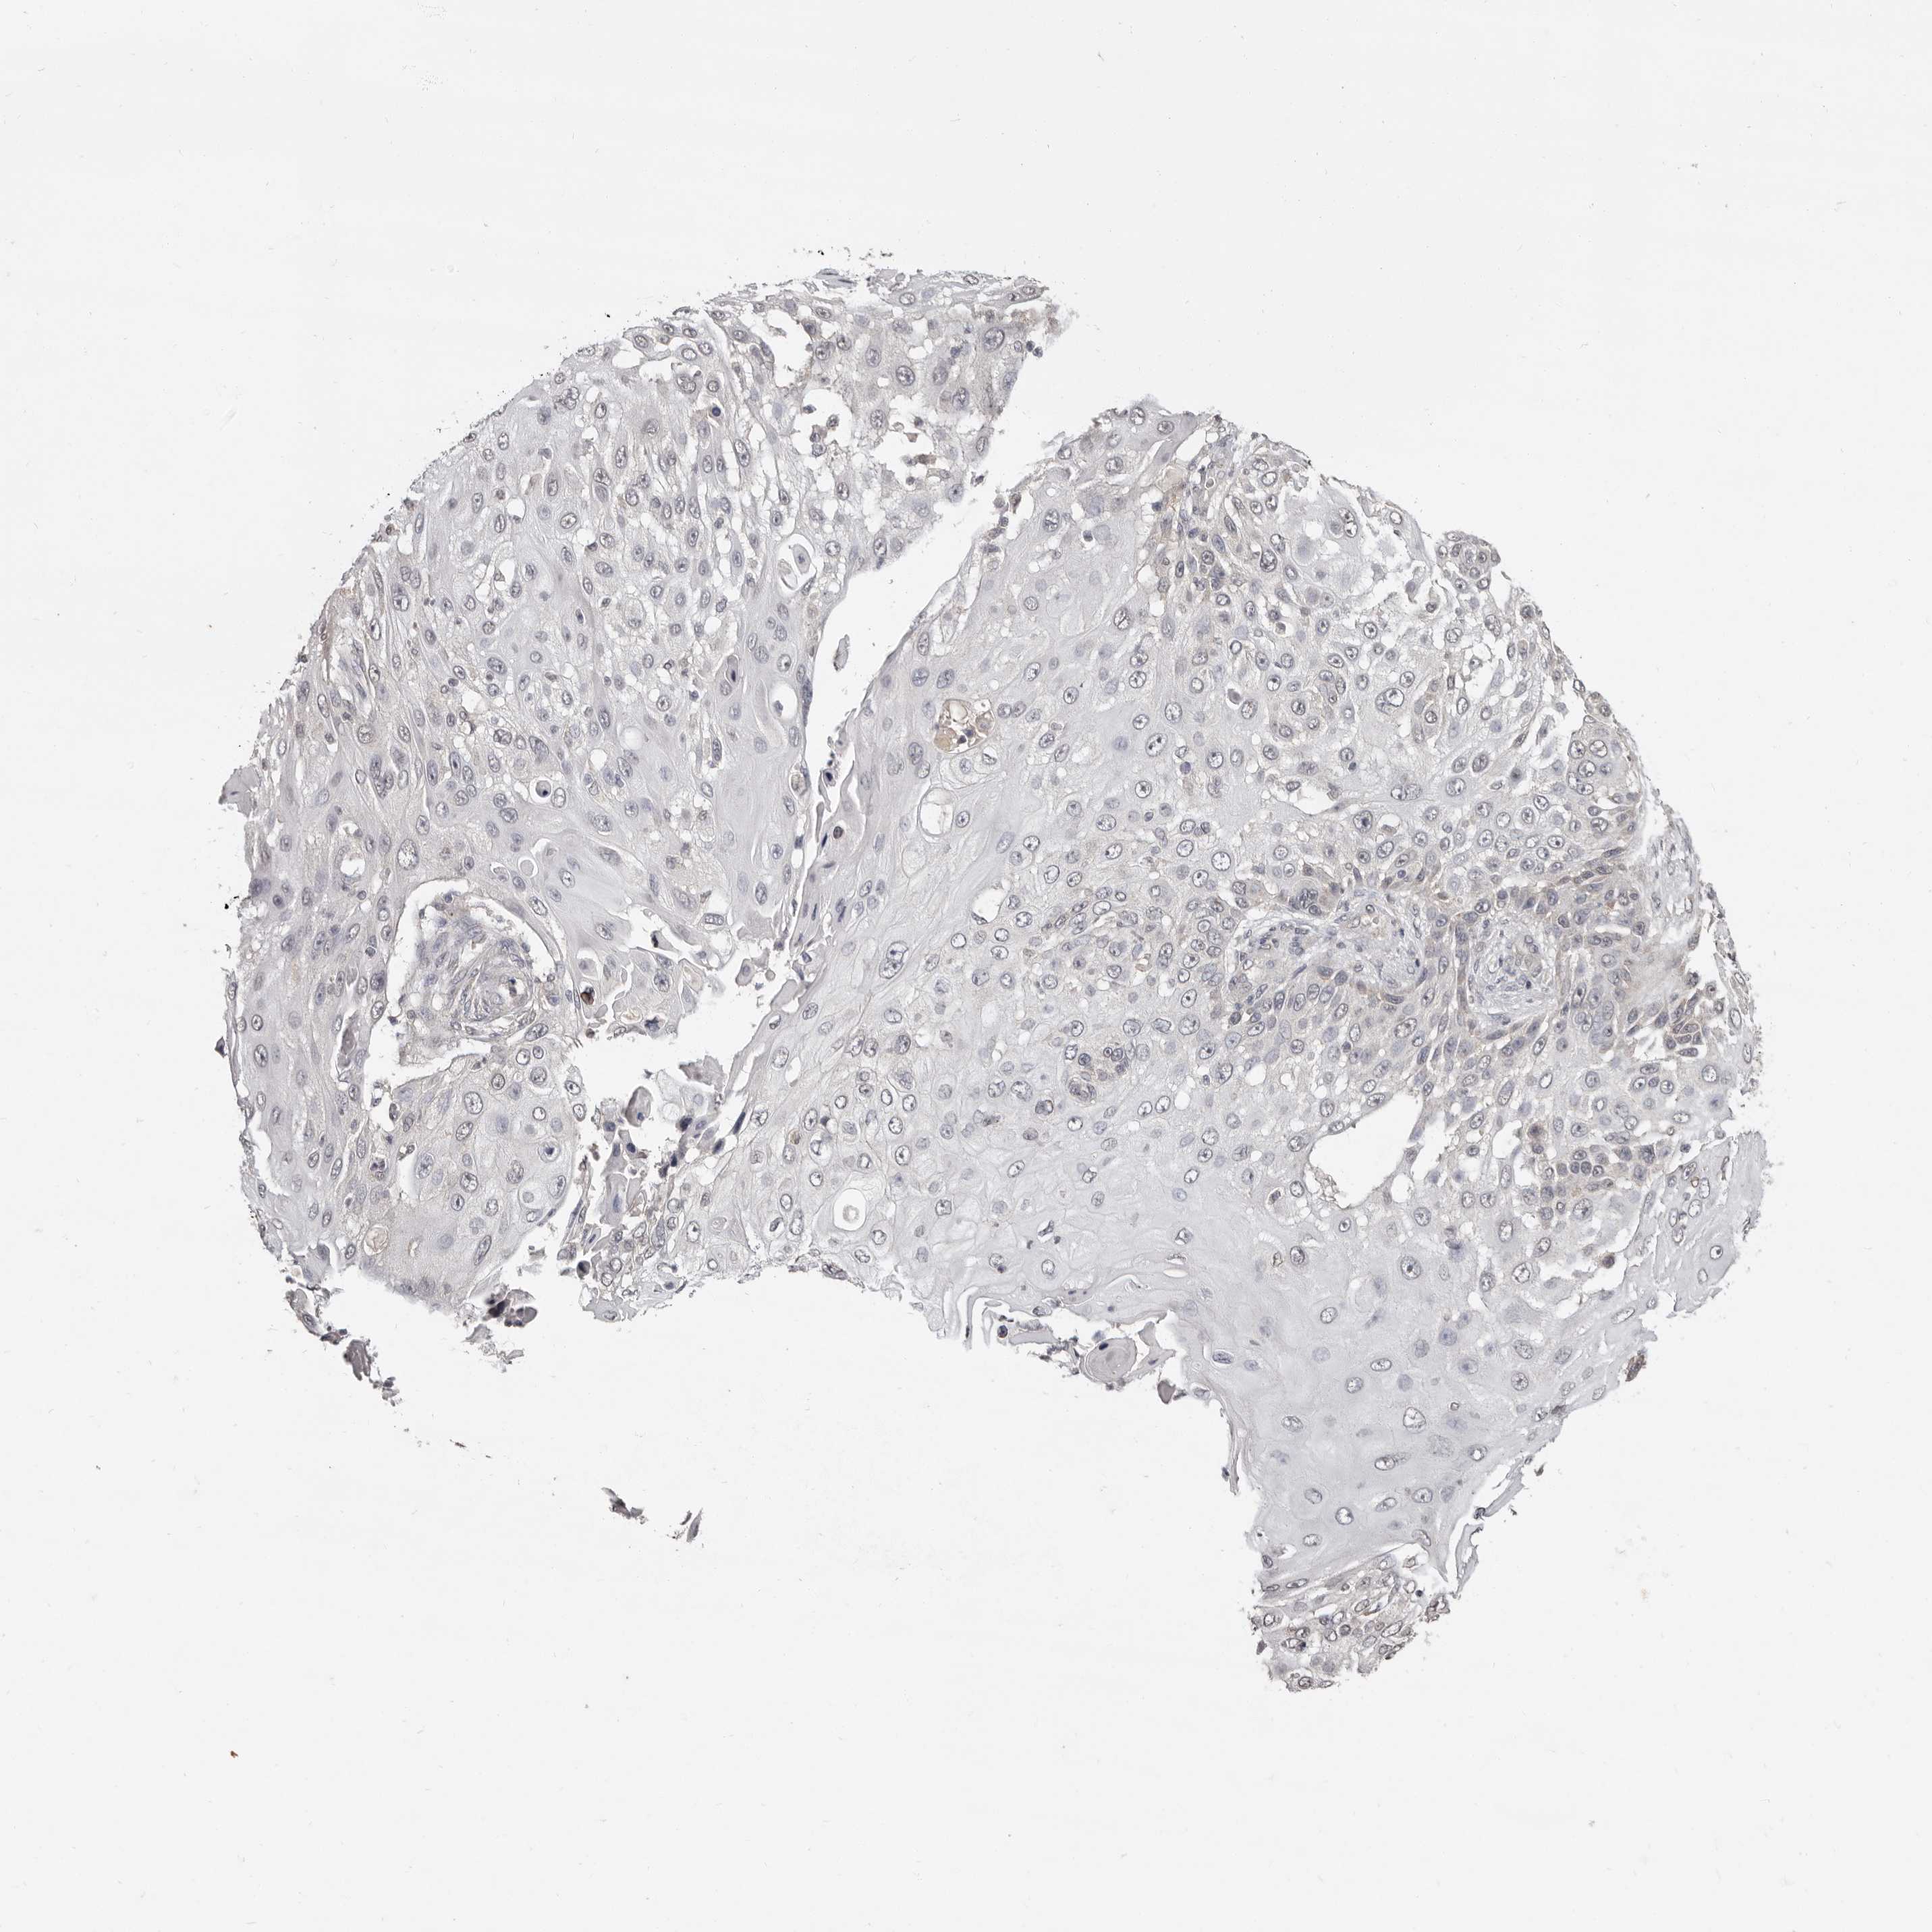

SKIN CANCER - Protein expressioni

A mouse-over function shows sample information and annotation data. Click on an image to view it in a full screen mode. Samples can be filtered based on level of antibody staining by selecting one or several of the following categories: high, medium, low and not detected. The assay and annotation is described here.

Antibody stainingi

Antibody staining in the annotated cell types in the current human tissue is reported as not detected, low, medium, or high, based on conventional immunohistochemistry profiling in selected tissues. This score is based on the combination of the staining intensity and fraction of stained cells.

Each image is clickable and will lead to virtual microscopy that enables deeper exploration of all samples and also displays staining intensity scores, fraction scores and subcellular localization as well as patient and tissue information for each sample.

Antibody CAB025361

Not detected

Negative

None

Basal cell carcinoma